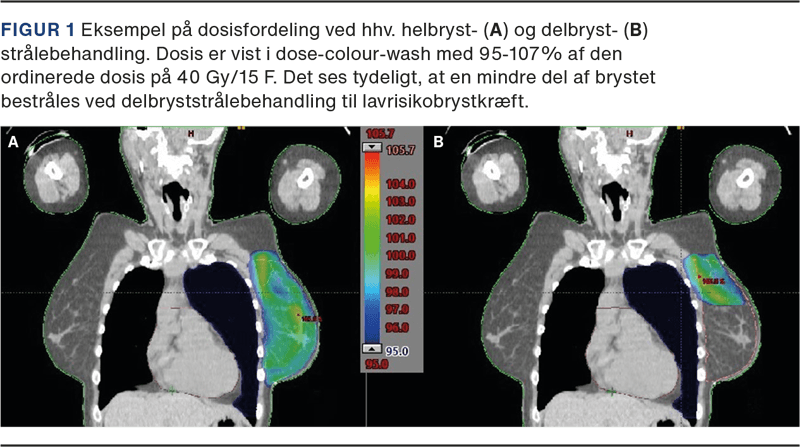

PBI tilbydes patienter med lavrisikobrystkræft, idet lokalt tilbagefald oftest findes inden for den samme kvadrant af brystet, som den oprindelige tumor var lokaliseret i. Ved PBI bestråles kun et begrænset volumen af brystet svarende til området omkring det oprindelige tumorleje (se Figur 1). Dette giver mindre fibrose samt en lavere risiko for senfølger på grund af en reduktion i hjerte- og lungedosis. PBI blev indført i Danmark i 2016 på baggrund af resultaterne fra DBCG’s PBI-studie [7] og det engelske IMPORT LOW [8]. I de to studier blev PBI ikke fundet dårligere end WBI og med en generelt meget lav forekomst af lokalrecidiv. Da der ikke er fundet signifikant højere risiko for tilbagefald ved PBI, taler hensynet til et bedre kosmetisk resultat og lavere risiko for senfølger for anbefaling af PBI hos lavrisikopatienter.

Til patienter med venstresidige tumorer og/eller ved lokoregional strålebehandling anbefales brug af respirationstilpasset strålebehandling (gating), idet dette kan reducere stråledosis i hjertets venstre ventrikelvæg og venstre koronararteries ramus interventricularis (se Figur 2). Ved gating gives kun behandling i inspiration. Herved forøges hjertets afstand til thoraxvæggen og dermed strålefeltet, ligesom en relativt mindre del af lungevolumen medbestråles [24]. Teknikken varierer fra simple metoder med frivillig, nonmonitoreret, dybt holdt inspiration til avancerede metoder med kontrolleret respiration med komplekst udstyr [25, 26]. Gating kræver ekstra apparaturressourcer, men har en høj patientkomplians og reproducerbarhed [27].